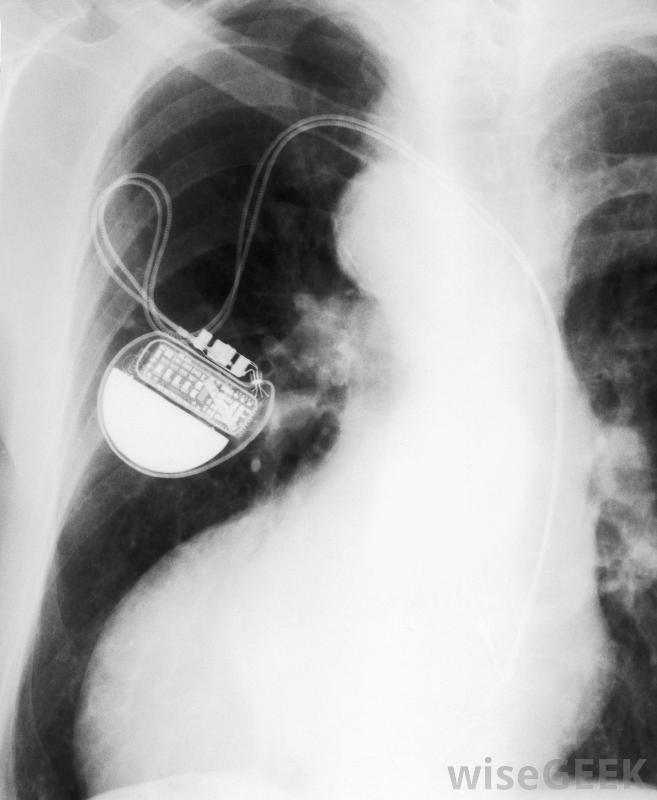

心律失常的患者需要起搏器的帮助。这些小装置被植入人体最重要的器官之一心脏附近。因此,诸如起搏器植入和可能的起搏器修复等问题通常需要特别关注。

评价起搏器的性能是起搏器临床的另一项重要功能。起搏器的工作原理是利用运动感测器,记录人体对氧气和其他生理必需品的需求根据患者的运动或休息速度,起搏器发出电脉冲,相应地加速或减慢心率。起搏器诊所的技术人员将跟踪起搏器在这些问题上的可行性,并跟踪起搏器的电池寿命。这些评估可以在现场进行,也可以通过连接起搏器进行通过电话线传输设备的统计数据。